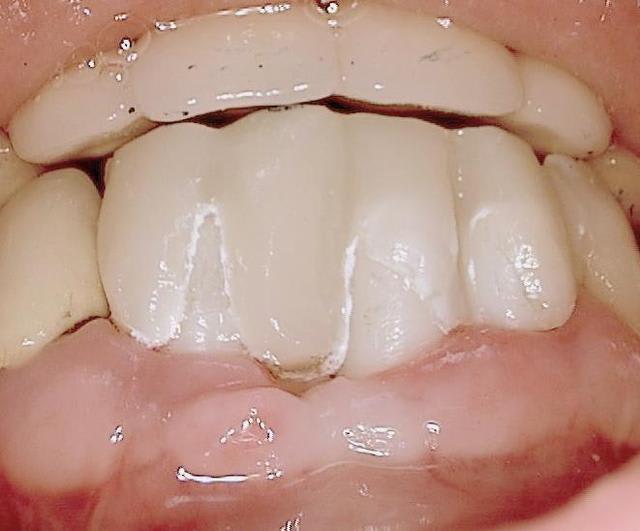

J'ai regardé toutes ces réhabilitations. Le truc qui me chiffonne dans tout ça (sur lequel je m'interroge, pour parler en français académique), c'est la façon dont on assure l'hygiène, avec des embrasures aussi petites et des prothèses qui semble bien proches de la gencive.

En bref : comment ça se nettoie ?

c est une bonne question (merci de m avoir expliquer le sens de chiffonne :-) l expression est marrante)

une bonne hygiène est surtout importante si le patient est malade par exemple suite à un "schlaganfall" (en allemand je ne sais pas le terme en francais)

les "vieux" systèmes deux pièces ont un micro espace de 30 micromètres , ce qui explique que les patients devaient nettoyer péniblement ...

en ceramique il n y a pas d accumulation de plaque donc pas de grandes concentration de bactéries gram negatif et anaerobie.La gencive se forme très bien autour de la ceramique ( la nature est le meilleur architecte!)

si après quelques années les couronnes sont retirées, on voit pas d infection....

pour finir c est sur qu il faut quand même se brosser les dents régulièrement. Les patients reviennent juste deux fois par an pour un nettoyage professionnel...

Oui tu as bien raison :-) Ci joint quelques photos en rapport avec ta question ....